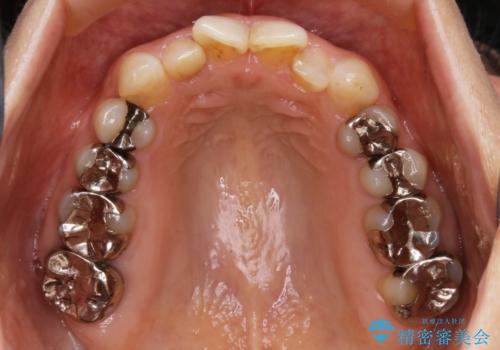

矯正装置の希望がインビザラインだったため、マイクロインプラントを併用し、奥歯から順に遠心移動をかけていくことにより非抜歯でも主訴のガタつきを治すことができました。

- 税込 ¥968,000- (インビザライン コンプリヘンシブパッケージ + マイクロインプラント費用)費用は治療当時の料金となります

マウスピースとマイクロインプラントを組み合わせることで、抜歯をしなくても歯並びを治すためのスペースを作ることができます。奥歯から順に移動させていくので前歯に変化が出るまでには時間がかかりますが、その分健康な歯を抜歯することなく理想的な歯並びを手に入れることができます。